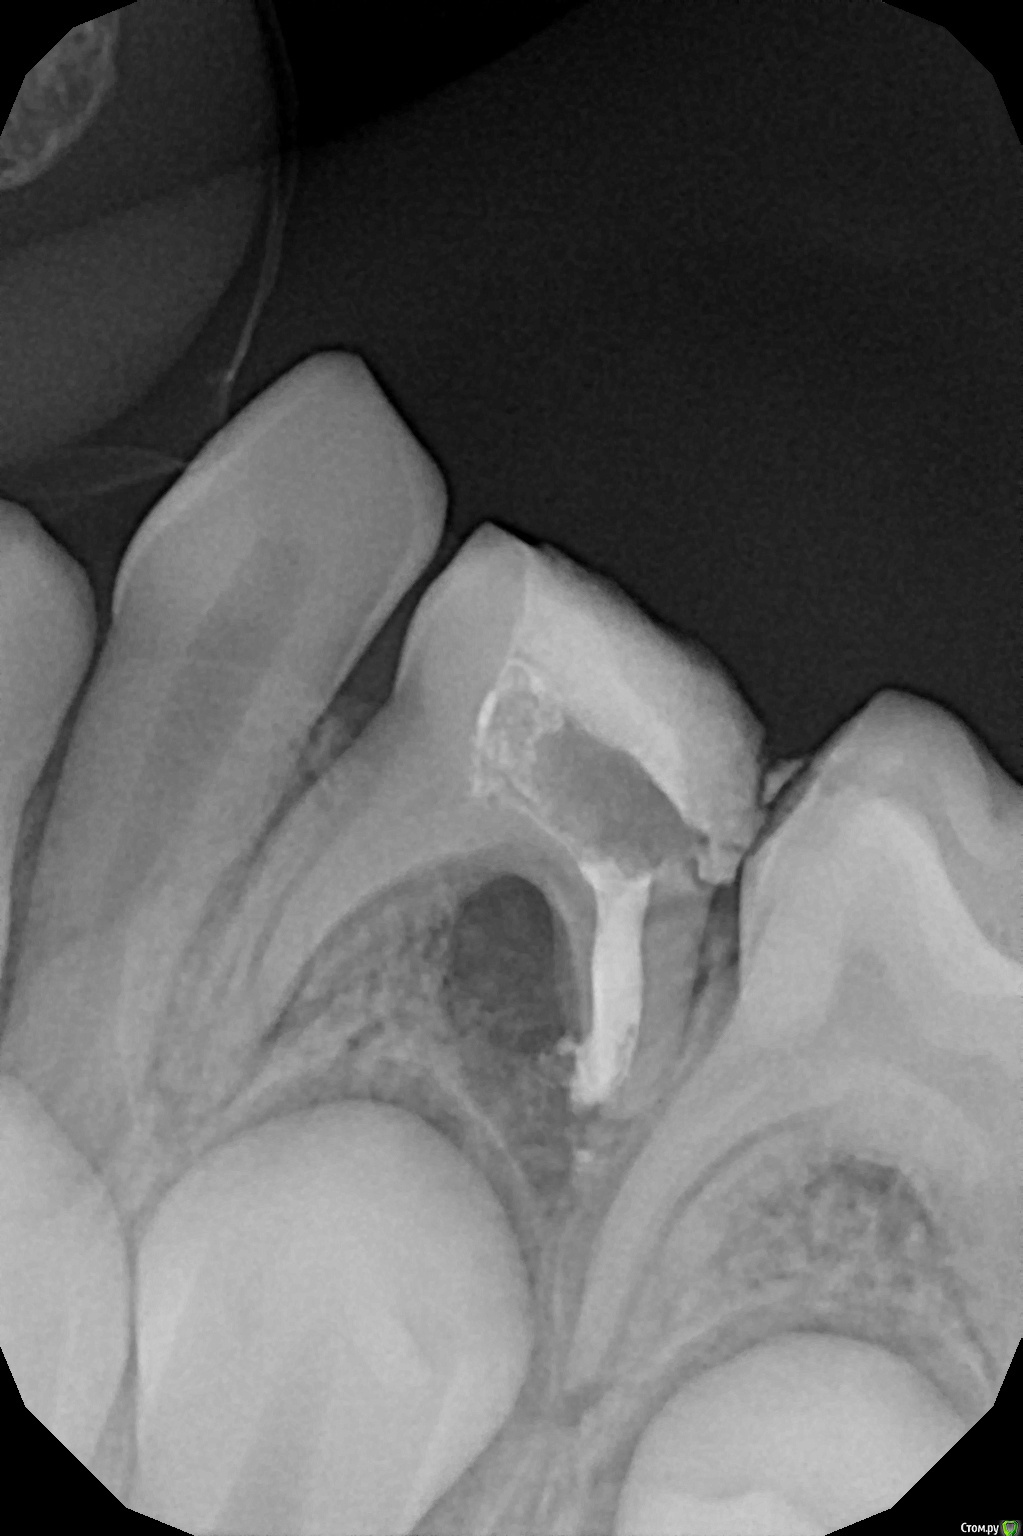

Wrestrus66 Опубликовано 8 декабря, 2016 Поделиться Опубликовано 8 декабря, 2016 Доброй ночи...))Пац : 7 лет , 74,75 жалоб никаких лечили около 3 лет назад ..Как быть ?! Ссылка на комментарий

crown Опубликовано 8 декабря, 2016 Поделиться Опубликовано 8 декабря, 2016 Убрал бы оба зуба. 74 однозначно, угроза зачатку, 75 туда же, слишком сильная деструкция, на кальцие боюсь не вытяните. Блин а че четверка то стрельнула? Мож канал пропустили... Ссылка на комментарий

Давлетшин Опубликовано 8 декабря, 2016 Поделиться Опубликовано 8 декабря, 2016 Если другой стороны есть вторичная адентия молочных, то есть смысл убрать оба и замещающую пластинку. Если с другой стороны норм все, то убрать четверку и понаблюдать динамику 3-4 мес. мне кажется от четверки такая сильная деструкция. 1 Ссылка на комментарий

Wrestrus66 Опубликовано 8 декабря, 2016 Автор Поделиться Опубликовано 8 декабря, 2016 завтра буду удалять 74.. т.к кортикалка уже задета ! а 75 под наблюдение ! Ссылка на комментарий

Джима Опубликовано 9 декабря, 2016 Поделиться Опубликовано 9 декабря, 2016 Не поняла логику про другую сторону и про пластинкук симметричной пластинке легче адаптироваться, односторонний съёмный держатель места на 7.4 и 7.5 носить никто не будет - зачем, можно ж на другой стороне жевать. поэтому, если проблема односторонняя, то потеря пятого зуба - штука серьёзная, надо сто раз хорошо подумать и по возможности сохранить. отакой парадокс.здесь, имхо, под 7.5 разрежение от 7.4. 7.4 убрать, 7.5 привести в порядок и наблюдать. 1 Ссылка на комментарий